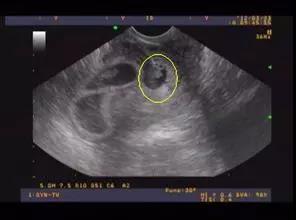

22周系统B超主要检查以下内容:

胎儿头部:观察胎儿大脑、颅骨、眼眶等结构是否正常。

胎儿心脏:检查心脏结构、血流情况,排除先天性心脏病。

胎儿腹部:观察肝脏、肾脏、胃、肠道等器官的发育情况。

胎儿四肢:检查四肢骨骼、肌肉等结构是否正常。

胎儿脊柱:观察脊柱是否有畸形,如蝴蝶椎等。

胎盘:评估胎盘的位置、成熟度、血流情况等。

通过这些检查,医生可以全面了解胎儿的生长发育情况,及时发现并处理潜在的问题。